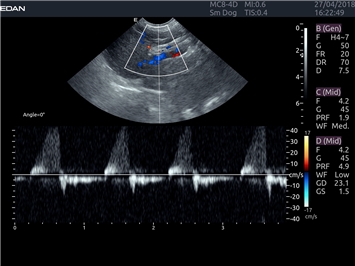

Постоянно-волновой допплер:

Да

Импульсно-волновой допплер:

Триплексное сканирование:

Дуплексное сканирование: